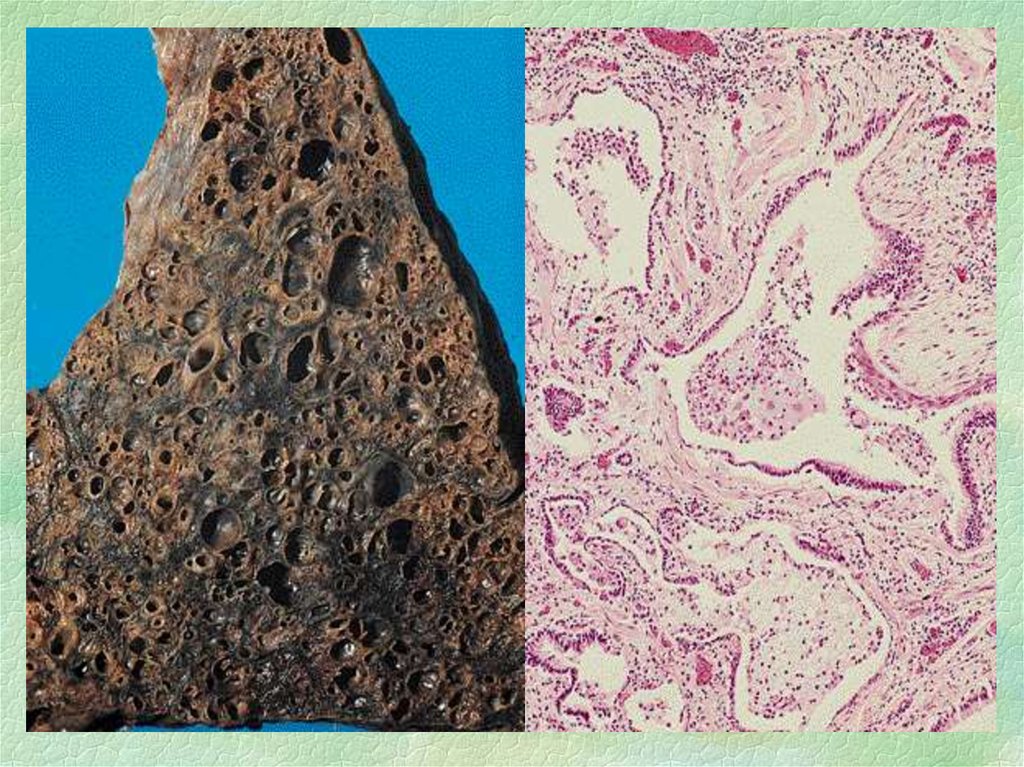

Микроскопический взгляд на мишитарный туберкулез легкого: фотодокументация

Раздел: Снимки-откровения